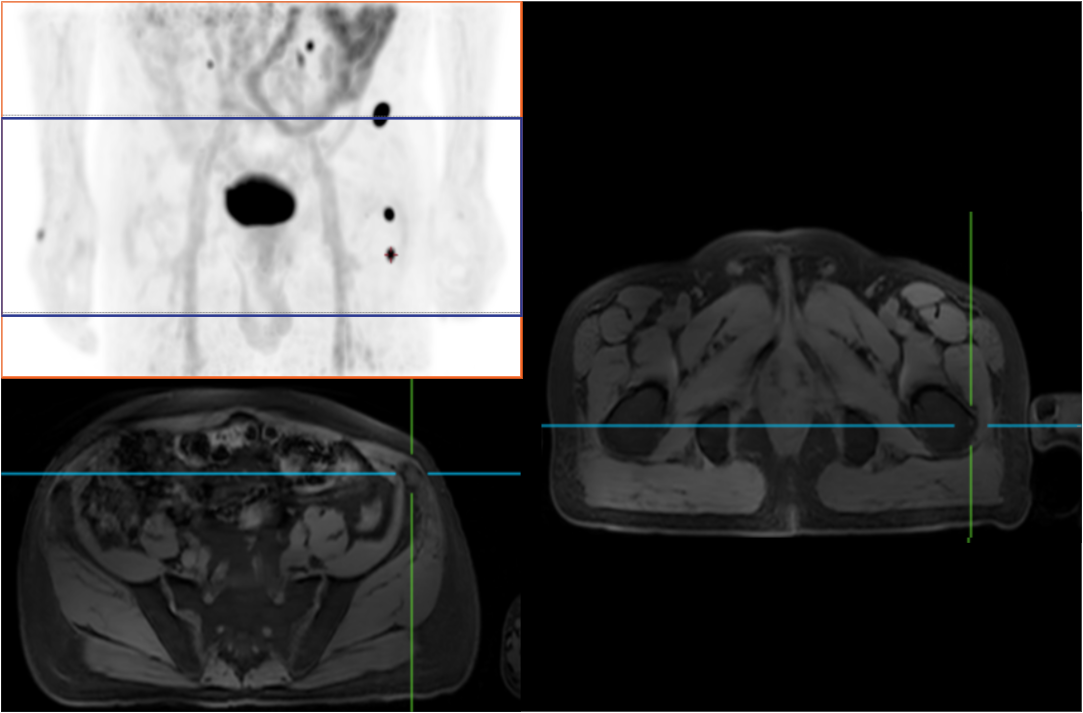

Compared with the conventional PET system with AFOV ranging between 20cm and 25cm, the 32cm long AFOV not only improves the sensitivity of the system, but also basically covers main organs of the whole body and the regional lymphatic system where metastasis may occur, and makes it possible to realize cancer TN staging in one bed position.

In August 2019, Peking Cancer Hospital introduced United Imaging Healthcare's integrated PET/MR to make an in-depth exploration and optimization of cancer TNM staging under long AFOV. More than 500 examples of scanning various organs proved that long AFOV PET/MR could greatly increase the scan range over one bed position and improve the efficiency of cancer TNM staging.

The following are the cases of optimized TNM staging of breast cancer, esophageal cancer, prostate cancer and other diseases under the long axial field of "spatio-temporal integration" ULTRA-clear TOF PET/MR.  Thanks to Capital Medical University Xuanwu Medical Treatment for providing the image.